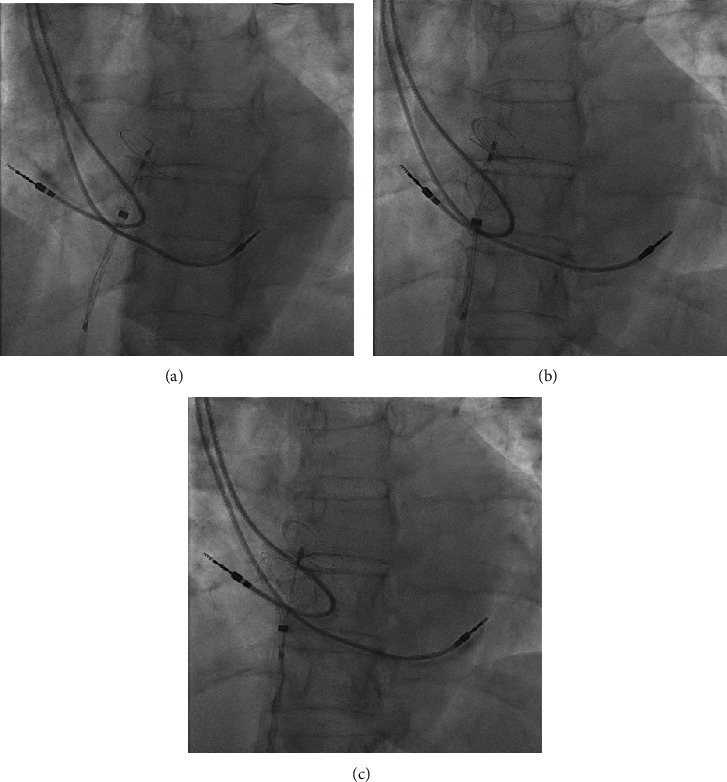

我们为您介绍一例可能因卵圆孔栓塞(PFO)引起的短暂性缺血性发作(TIA)患者。她的病史包括二度心脏传导阻滞 Mobitz II,表现为反复晕厥,曾接受双腔起搏器治疗。在 PFO 介入封堵术中,我们注意到心房起搏器导线被夹在右侧封堵器圆盘和房间隔之间。我们使用一个 24 毫米大小的球囊成功地将导联移至一侧,随后将右侧封堵器盘开发到正确位置。总之,使用尺寸调整球囊可以防止起搏器导联夹在 PFO 闭塞盘和房间隔之间。

We present a case of a patient with a transient ischaemic attack (TIA) likely due to paradoxical embolism through a patent foramen ovale (PFO). Her medical history included 2nd-degree heart block Mobitz II, which manifested with recurrent syncopes and was treated with a dual chamber pacemaker. During the interventional PFO closure procedure, we noted entrapment of the atrial pacemaker lead between the right-sided occluder disc and the interatrial septum. We were able to successfully move the lead aside using a 24 mm sizing balloon and subsequently developed the right-sided occluder disc in the correct position. In conclusion, pacemaker-lead entrapment between a PFO occluder disc and the interatrial septum can be prevented using a sizing balloon.